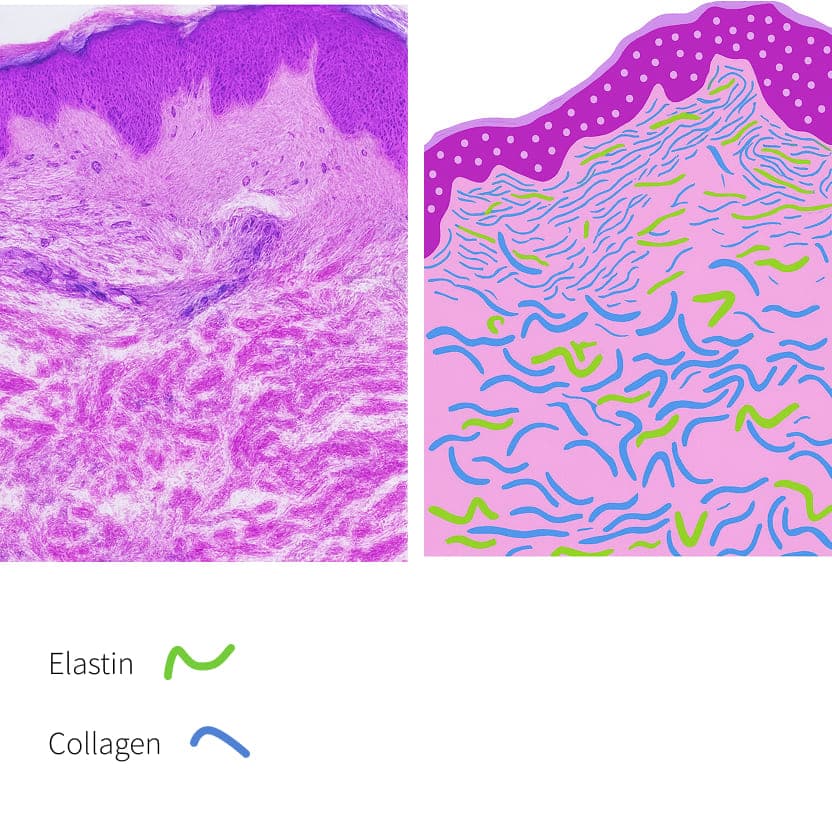

Einführung in Dehnungsstreifen

Normale Haut

Smooth and elastic with intact collagen and elastin fibers maintaining firmness and structure.

Striae Rubrae

Early red or pink stretch marks caused by dermal tearing and inflammation with visible blood vessels.

Striae Albae

Mature white stretch marks where collagen remodeling leads to thinning and loss of pigmentation.

Wirkmechanismus:

- Fördert die Entfernung von altem geschädigtem Kollagen

- Induktion von Keratinozytenproliferation, die Wachstumsfaktoren freisetzt, um die Kollagenablagerung durch Fibroblasten- und Elastinablagerung zu fördern

- Moduliert die Expression mehrerer Gene in der Haut (vaskulärer endothelialer Wachstumsfaktor, Fibroblasten-Wachstumsfaktor, epidermaler Wachstumsfaktor, Kollagen Typ I und III), welche die extrazelluläre Matrix-Remodellierung fördern